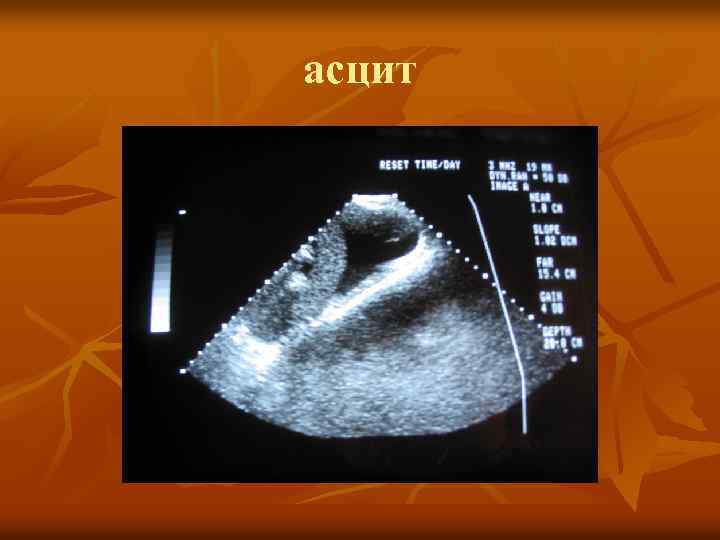

асцит асцит

УЗИ асцит УЗИ асцит